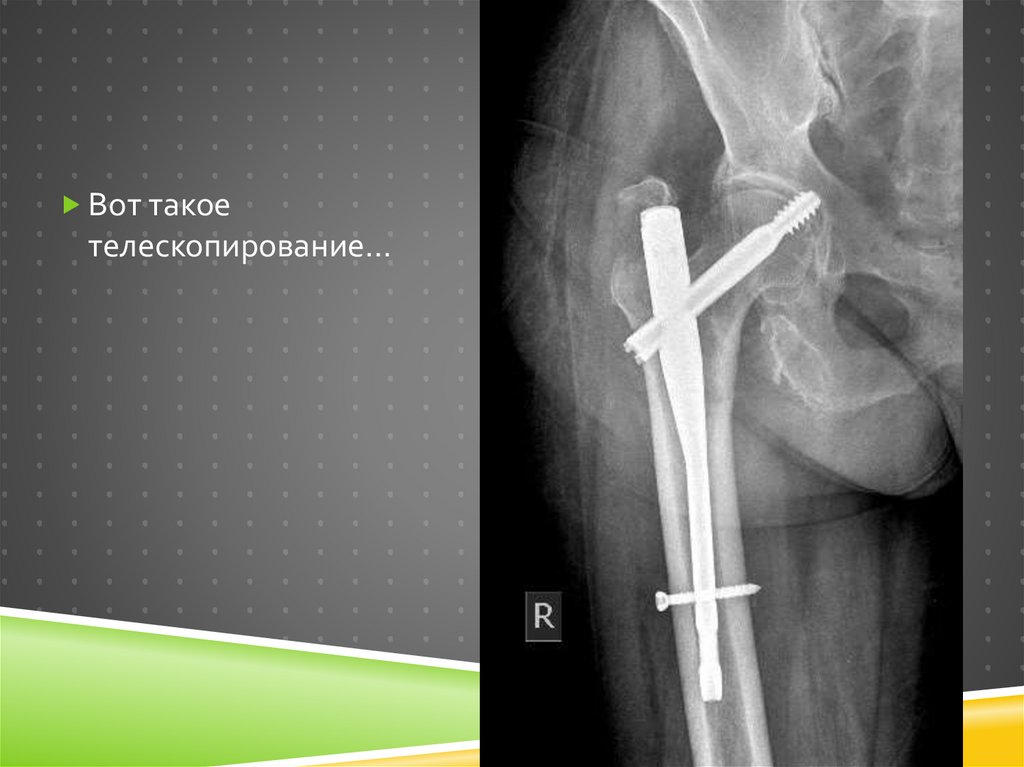

126.

Вот такое

телескопирование…